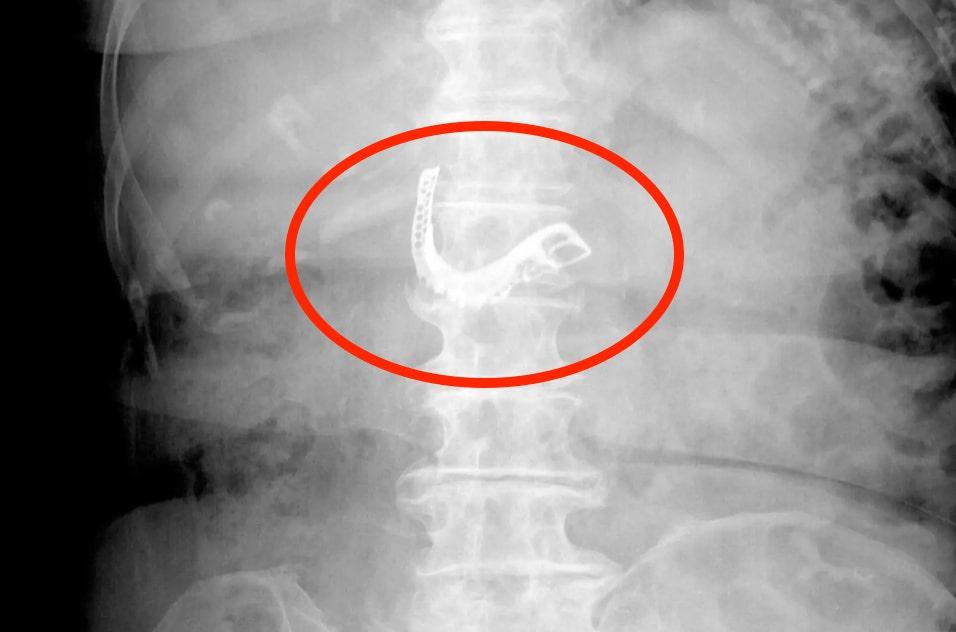

Gambar dari kamera internal dengan sangat jelas menunjukkan gigi palsu berada di dalam perutnya. Pemindaian pada tubuhnya juga menunjukkan lengkungan gigi palsu yang sangat menonjol pada struktur kerangkanya.